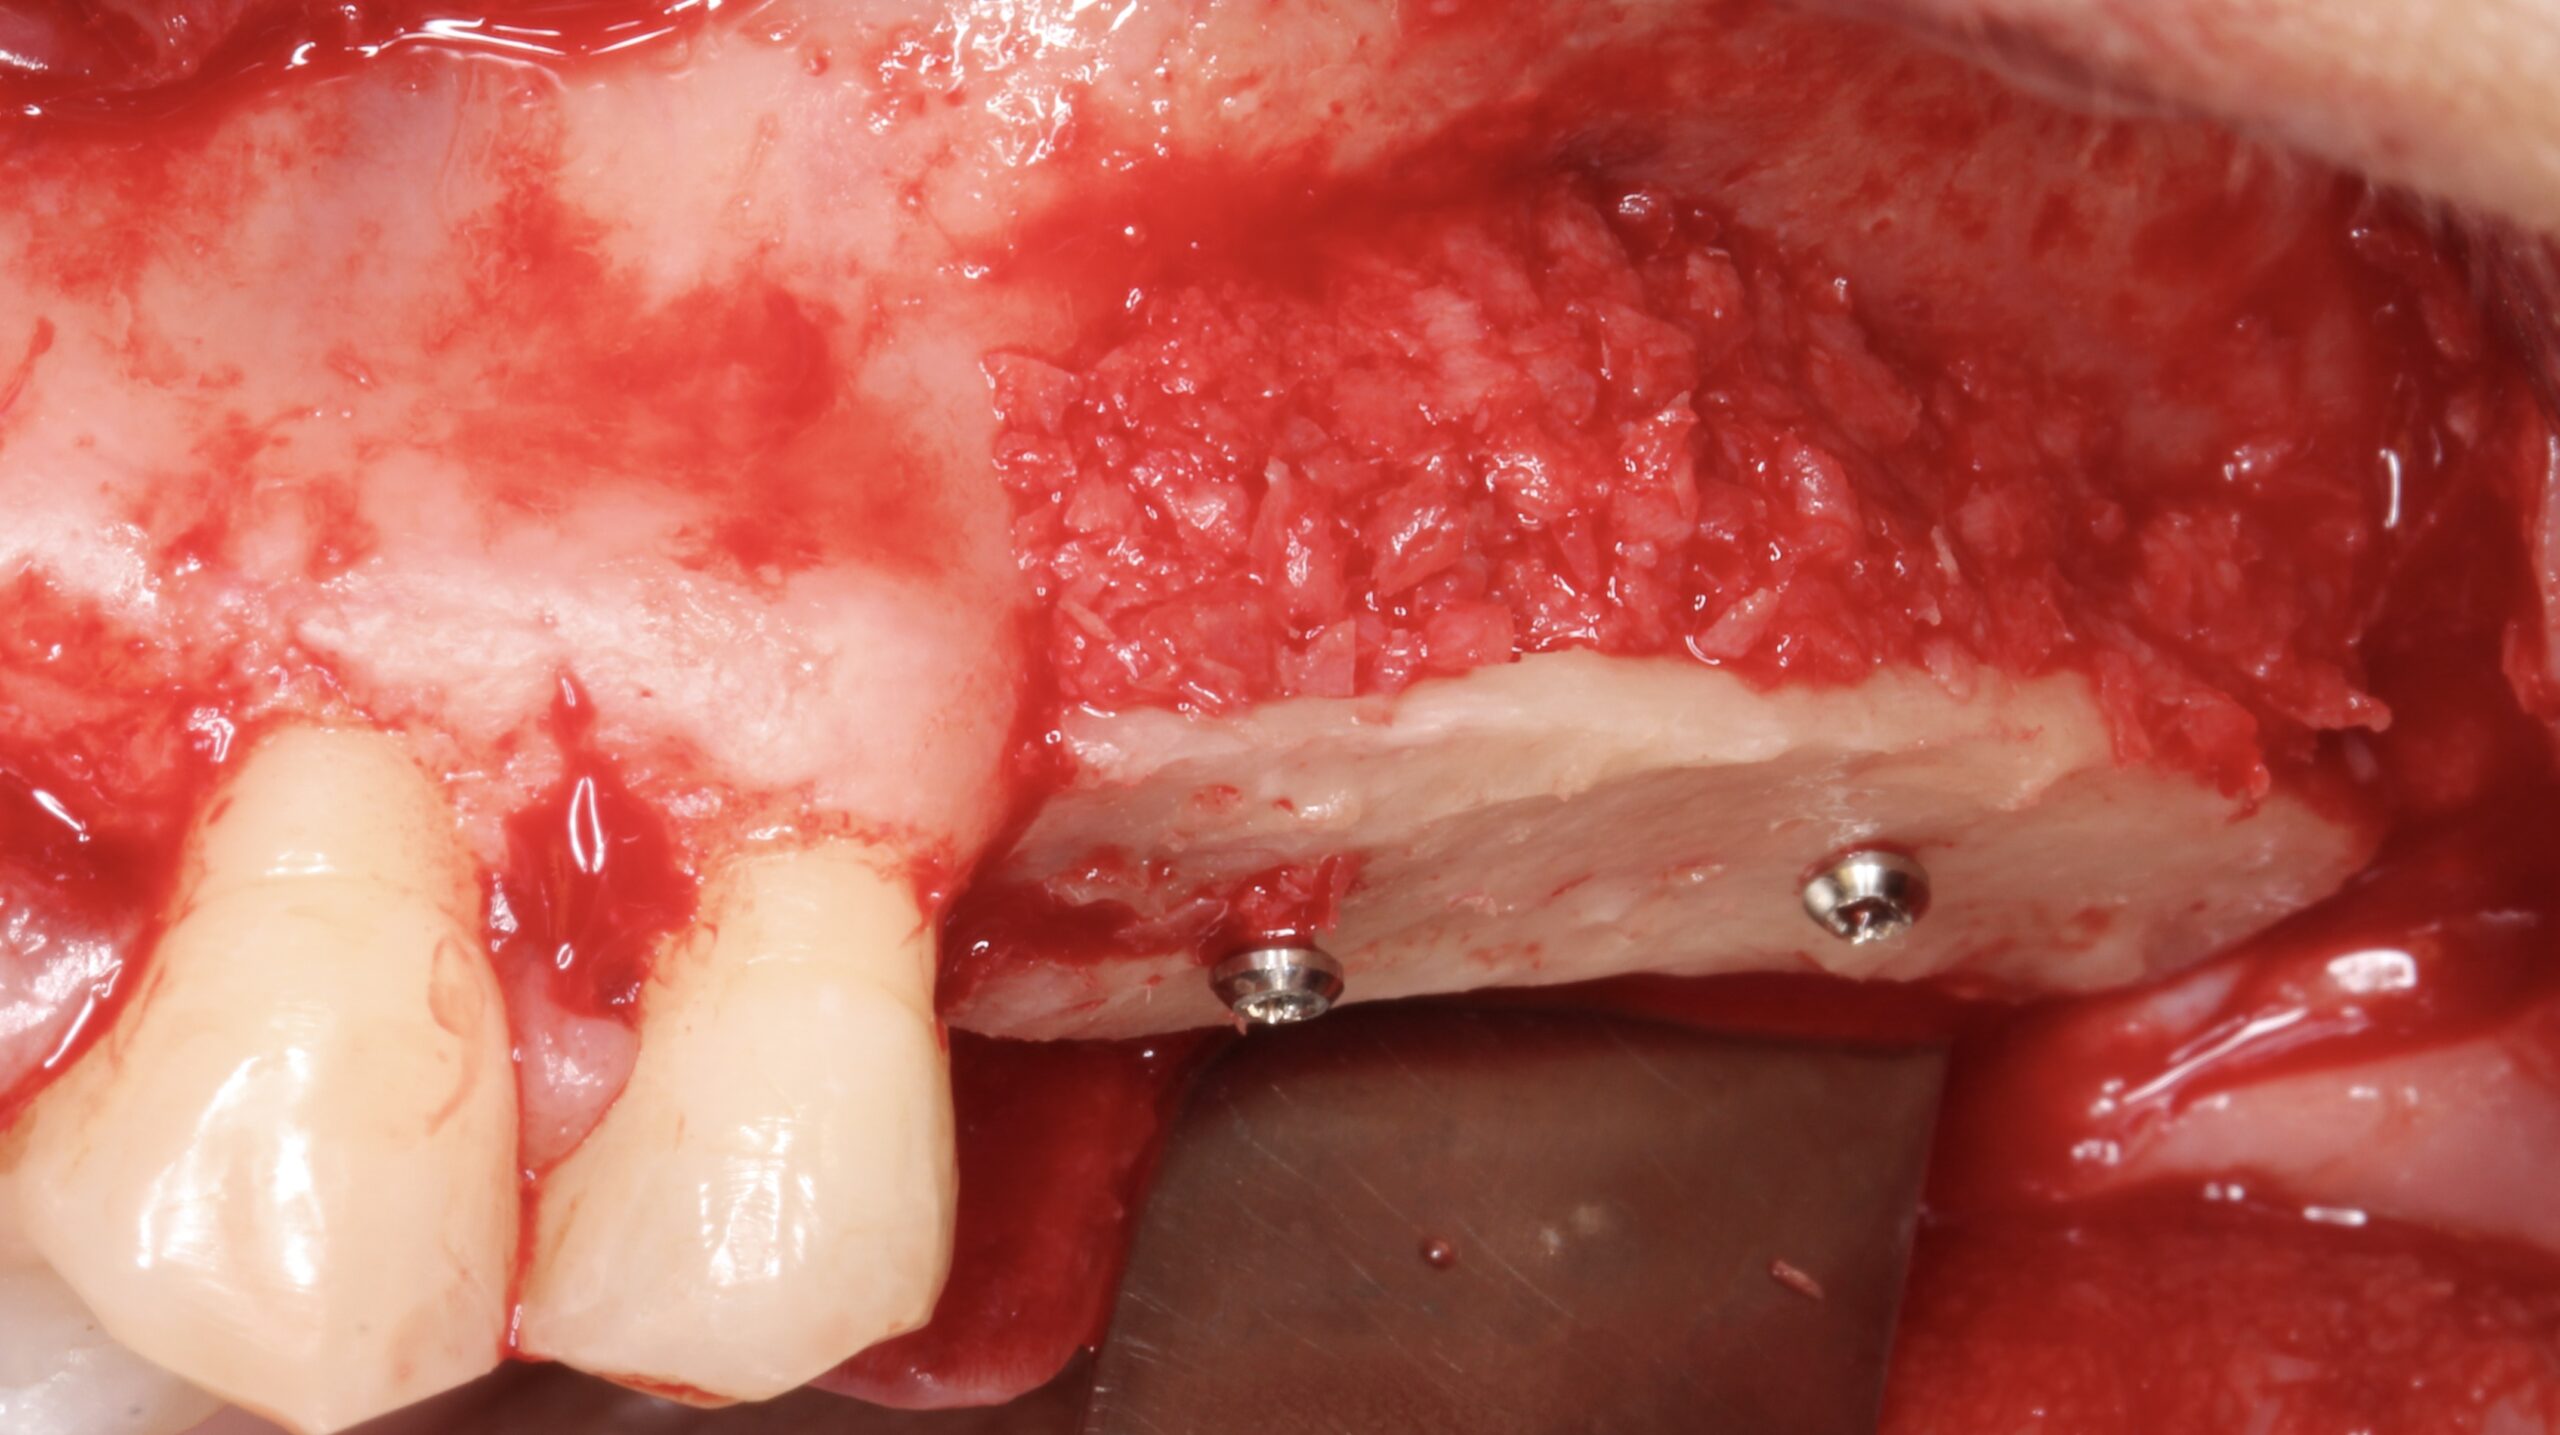

A split bone block was fixed by screws at the coronal aspect of the alveolar ridge from peak to peak.

Figure 6.

The gap between the block and the alveolar ridge was filled with scraped bone chips.